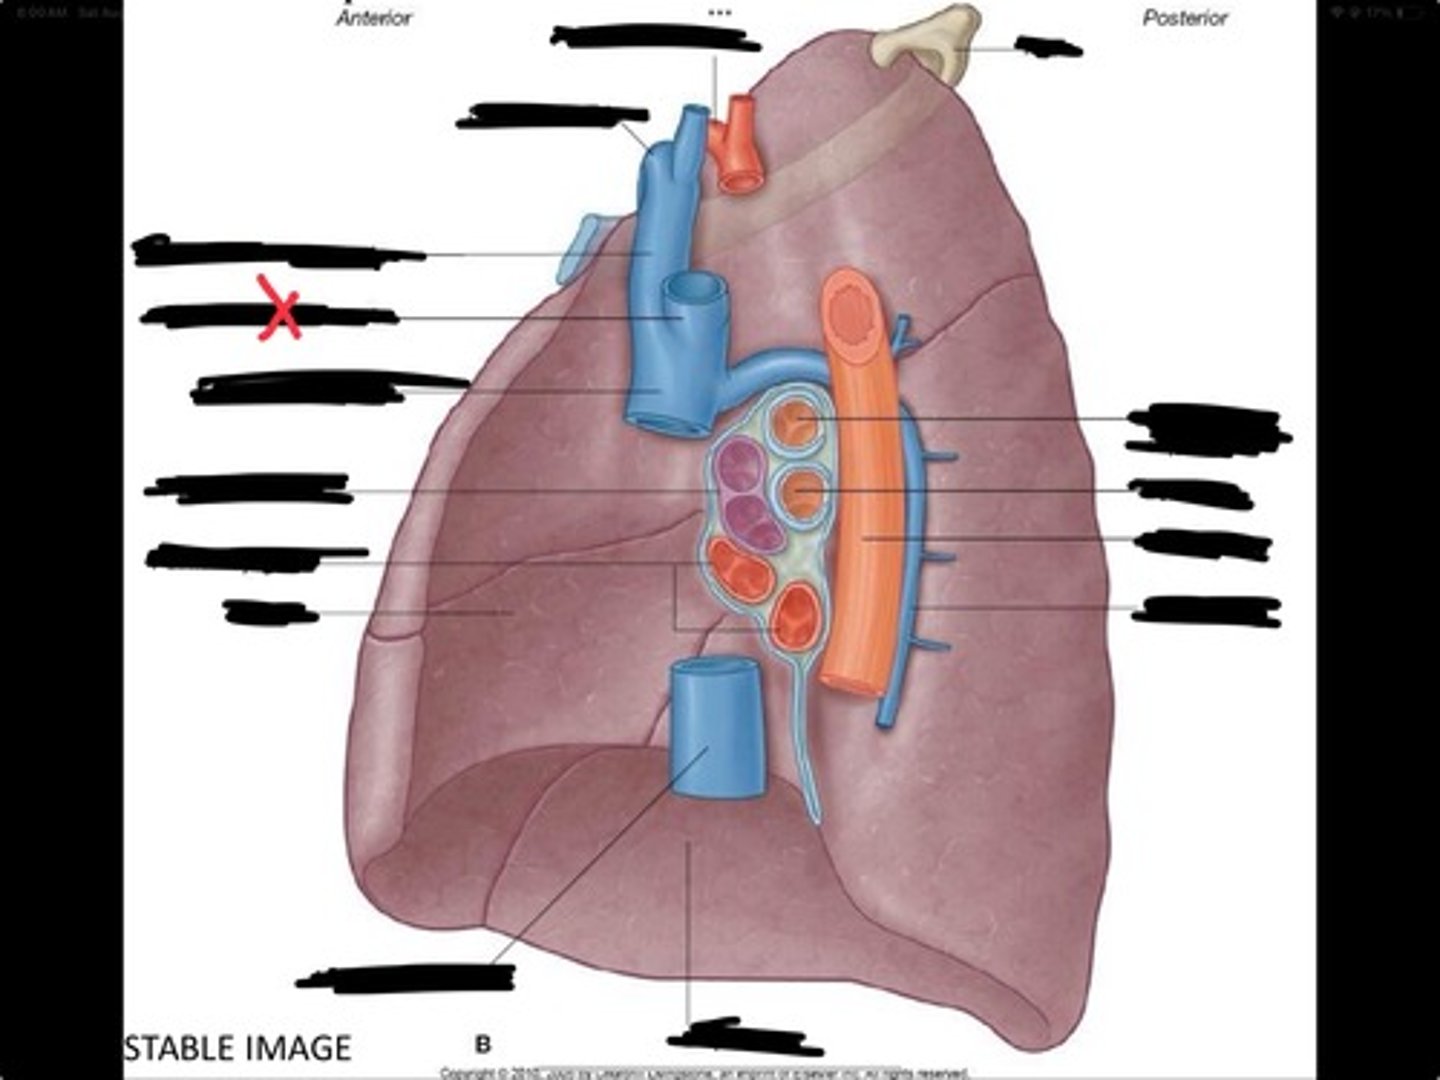

Diaphragm

Inferior vena cava

Superior vena cava

Subclavian vein

Right bracheocephalic vein

Subclavian artery

Esophagus

Bronchus

Rib 1

Left subclavian artery

Left brachiocephalic vein

Aortic arch

Pulmonary artery

Pulmonary vein

Heart

Left brachiocephalic vein

Azygos vein

Esophagus

Bronchus

Fibrous pericardium

Parietal layer of serous pericardium

Pericardial cavity

Visceral layer of serous pericardium

Junction between fibrous pericardium and adventitia

Heart

Thoracic aorta

Rib 1

Pulmonary artery

Bronchus to superior lobe